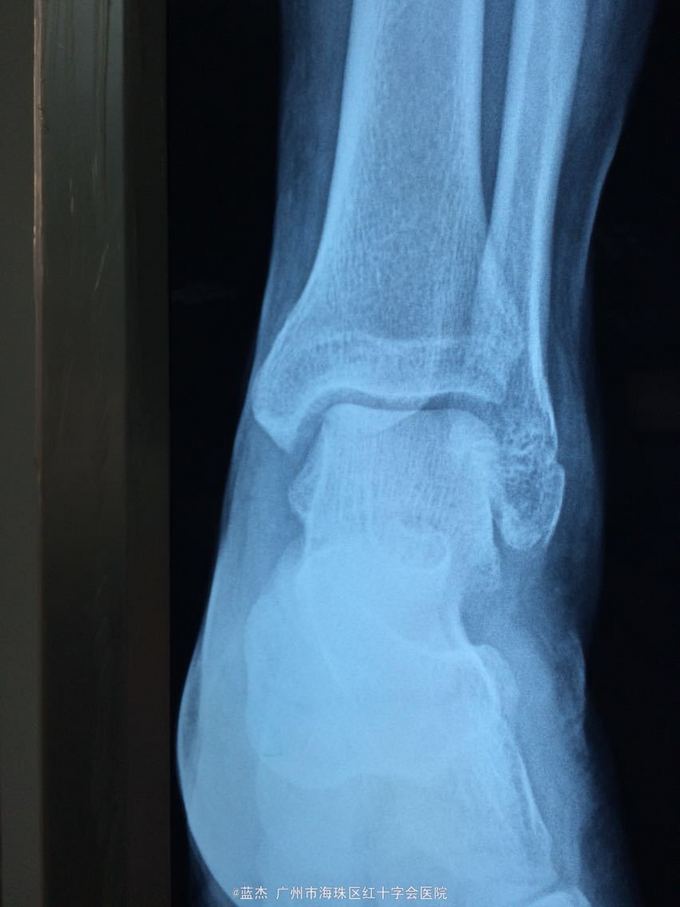

主诉:左踝关节疼痛肿胀伴有活动受限6小时。 病史:患者6小时前打篮球时不慎扭伤左踝关节,致使左踝关节疼痛,肿胀,伴有活动受限。遂到xx骨伤科医院就诊,接诊医生建议患者手术治疗,患者本人考虑到可以保守治疗,签名拒绝手术治疗后,遂来我院治疗,现见患者左踝关节外侧疼痛,肿胀,活动受限,无其他不适。

查体:左踝外侧压痛,左踝的背伸,跖屈功能可。

诊断:腓骨骨折 处理:外敷双柏散膏+小夹板固定,口服活血止痛汤7剂。每隔2天换一次药。

随访:一月后复查X片,骨折处对位对线良好,功能活动度可,肿胀消除,可正常下地行走,少许疼痛。行去除小夹板,继续外敷药+骨科外洗药治疗,7周后行走正常,疼痛基本消失。 讨论:请问各位医生,这种情况在大医院或者专科医院是不是一定要手术治疗?有些时候保守治疗的效果也是不错的。